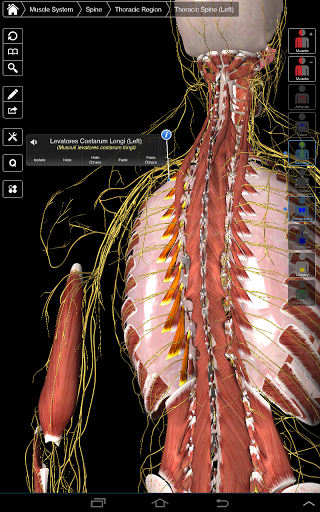

Основна анатомія 3 - це найновіша технологія та новаторський дизайн. Ріжучий 3D-графічний движок, зроблений на замовлення 3D4Medical з усього світу, наділений високоінформативною анатомічною моделлю і забезпечує високу якість графіки, яку не може досягти ніхто інший конкурент.

Програма являє собою унікальний підхід до вивчення загальної анатомії. Графіка не має аналогів і навчається, використовуючи інформативний контент та інноваційні функції, багатий та захоплюючий досвід.

⁃Маски

⁃Nerves

НОВІ 3D-ТЕХНОЛОГІЇ

Основна Анатомія 3 чутлива, візуально приголомшлива і легка. Додаток повністю 3D, що означає, що ви можете переглядати будь-яку анатомічну структуру окремо, а також з будь-якого кута.

Безперервна навігація та функціональність

Розумна функціональність, знайдена в додатку, дозволяє користувачеві знімати шари м'язів за допомогою інструмента «скальпель». Ця програма надає користувачам можливість увімкнення / вимкнення систем без необхідності скасувати вибір окремих структур або переплутати через безліч попередньо визначених регіональних вкладок, як і інші програми.

---- Більше 4000 дуже детальних анатомічних структур

---- Латинська номенклатура для кожної анатомічної структури